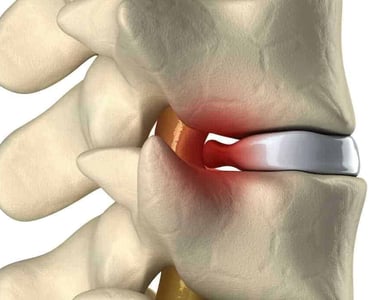

Cirugía de columna

Dolor de cuello

Dolor de espalda

Ciática

Hernia de disco

Cirugía mínimamente invasiva